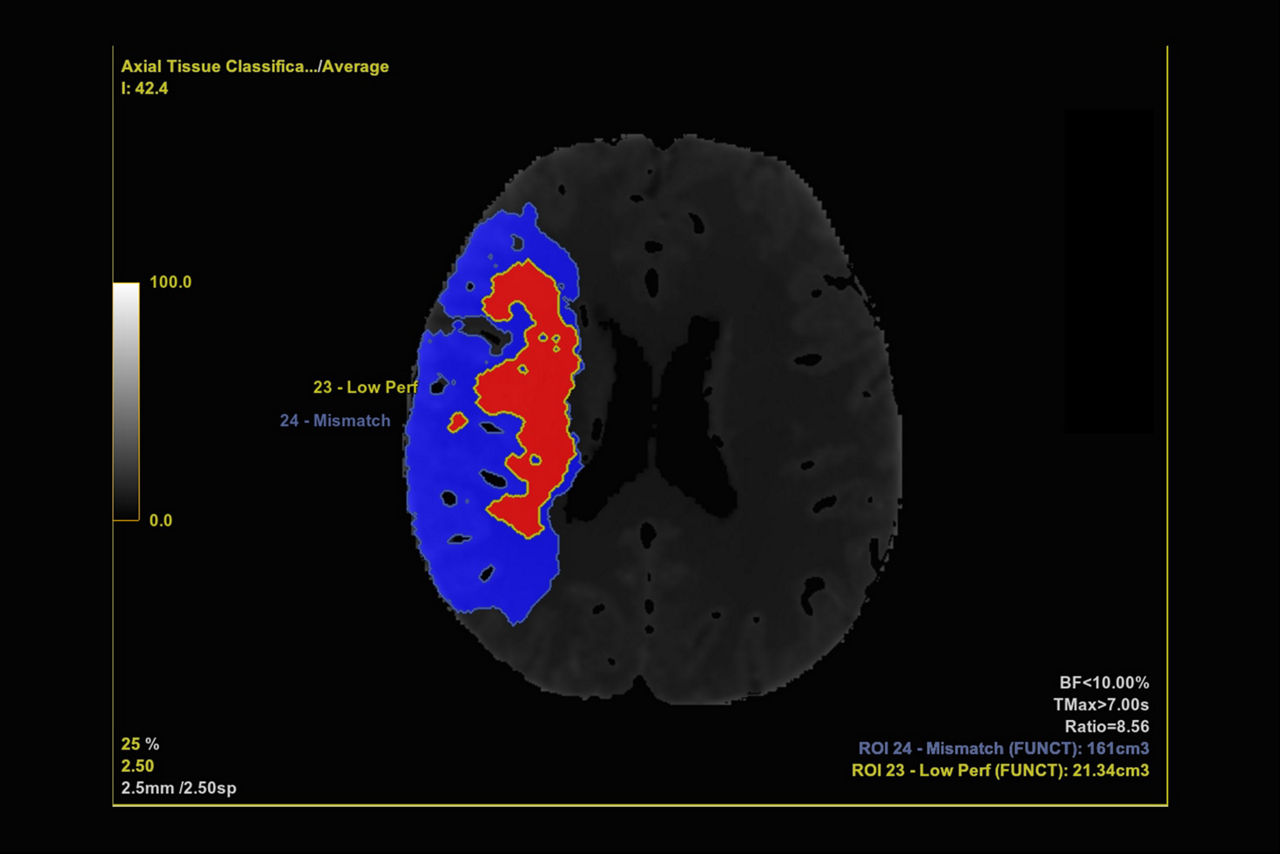

Brain stroke protocol

• Tissue Classification enables the visualization of regions that are segmented from absolute or relative values, customizable thresholds and user selectable input maps

• Mismatch volume and ratio are calculated from the modified perfusion volume and low perfusion volume ROIs